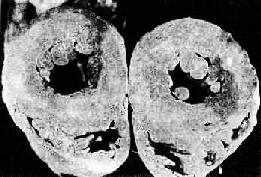

常出現紫紺伴肺充血或缺血。心臟聽診均有噴射性或收縮期雜音。心電圖檢查:常見左心室肥大。右心導管檢查及選擇性左心室造影和切面超聲心動圖檢查為主要診斷方法,在主動脈和肺動脈的血氧飽和度幾乎相等,在左心室造影見兩根大動脈同時顯影。